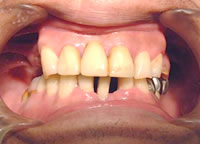

症例2 2007 1/11 更新

治療前 治療完了

治療前

平成17年3月18日

治療完了

平成18年12月18日

(治療期間:1年9ヶ月)